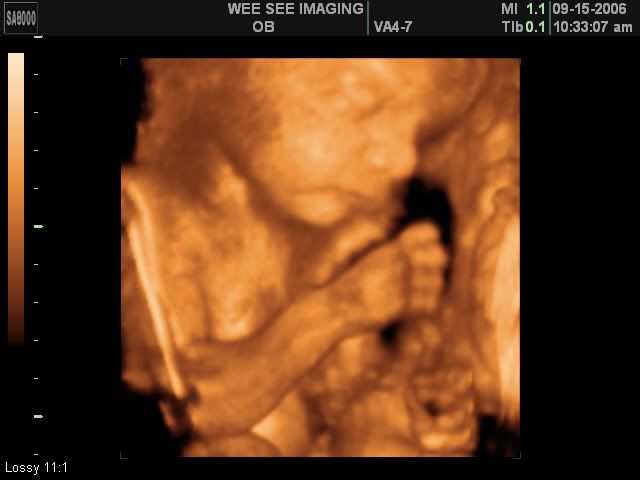

Victoria Rose Kelly

Date Due: December 15, 2006